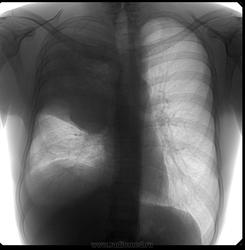

Мужчина 28 лет. Болен около месяца. В первую неделю заболевания была лихорадка. Практически не лечился. Всё время работал.

Беспокоит сильный кашель, 2 недели назад с гнойно-кровянистой мокротой, последние дни кашель до рвоты, из-за которого почти не ест и может спать только на правом боку, мокрота скудная, светлая. Похудел, слабость, одышка при небольшой нагрузке.

Сегодня решил проверить своё здоровье на флюорографии. Предыдущая флюорография 6 лет назад.

центральный рак, ателектаз верх. доли

На мой взгляд, центральный рак + параканкрозная пневмония + базальный параканкрозный плеврит.

"может спать только на правом боку"-патогномоничный признак полости(-ей). предположу: была пневмония (лихорадка),к-ая абсцедировалась (не лечился).абсцесс прорвался (мокрота,кашель до рвоты), содержимым обтурировался в\д бронх,вследствие чего возникла гиповентиляция верхней доли. Ну и экссудативный плеврит в довесок

Я рассуждал почти также. Только настоящего ателектаза, пожалуй, нет. Написал: "Абсцедирующая пневмония без дренирования абсцесса в настоящее время, с ателектатическим компонентом. Экссудативный плеврит есть и свободный и осумкованный. Линейку сделать можно, но надо сперва пролечить, получить динамику. Для начала в прорыв брошена кавалерия…, ну терапевты, значит.

Поддержу недренированный абсцесс/абсцедирующую пневмонию. Ну, и гидроторакс, конечно.

Интересное наблюдение. Поддерживаю 3 последних поста. ИМХО:скиологически, корректно  вести речь, о выраженном выпоте в плевральной полости с осумкованием, частичном  компрессионном ателектазе верхней доли.Субстратом пневмонии, по видимому является округлый инфильтрат в прикорневом отделе ( абсцесс который конечно, недренировался, т.к. в случае дренирования был бы виден уровень жидкости) и  перибронхиальная инфильтрация в нижнем поле.

При недренированном абсцессе такого размера у молодого человека была бы лихорадка под 40 и не только в первую неделю заболевания. Как вариант предлагаю рассмотреть саркому правого лёгкого.

доб.сн.: на прямом и на боковом - симптом ампутации в\долевого бронха= явление ателектаза в\доли, в которой начался распад (участок просветления на прямом). Центральный...как-то сомнительно, лимфосаркома...и всего 28